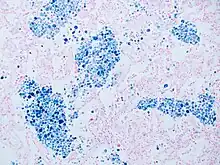

Coloration de Perls

La technique de Perls est une technique de coloration cytochimique de tissus utilisée en hématologie. Elle permet de mettre en évidence le fer fixé dans l'hémosidérine colorée en bleu par le bleu de Prusse[note 1] ; les noyaux sont mis en évidence par le rouge nucléaire.

La coloration de Perls est majoritairement employée pour diagnostiquer les syndromes myélodysplasiques par l'identification de sidéroblastes en couronnes sur les myélogrammes. Ces cellules sont des globules rouges immatures dont les granulations d'hémosidérine entourent le noyau[2].

La coloration peut également servir dans l'exploration des anémies pour évaluer la localisation et le métabolisme du fer[3],[4]. Les corps de Pappenheimer sont aussi visualisables[5],[6].